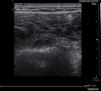

Figure 1.

Destructuring and increase in volume of the muscle fibres of the biceps brachii, with associated haematoma of 6cm; thickening and free fluid of the tendon of the long portion of the biceps.

The suspected diagnosis was a probable rotator cuff injury but, due to the striking clinical manifestations, the following complementary tests were carried out: analytical tests, of which we include and highlight D-Dimer assay 309ng/ml, correlated with the Wells score, with high probability of thrombosis (score3), fibrinogen 480mg/dl, 100% prothrombin activity 100%, CPK 421<IU/l, CPR 1.6mg/dl; as well as shoulder ultrasound and upper limb venous Doppler ultrasound. The ultrasound findings were described as destructuring of the muscle fibres and increase in volume of the proximal and middle third of the biceps brachii in relation to extensive fibrillar tear with associated haematoma of 6cm and tendon of the long portion of the biceps with thickening and free fluid, compatible with partial tear (Fig. 1). In addition, occupation of the partial axillary vein in a segment of some 40mm compatible with thrombosis (Fig. 2). Permeable internal jugular, subclavian, humeral, basilic and cephalic vein, with no signs of DVT.